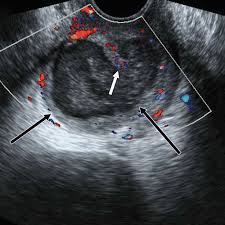

Digestive Diseases Mimicking Primary Gynecological Diseases Or With Secondary Gynecological Manifestations Sciencedirect from ars.els-cdn.com Can ovarian cancer be found early? Guide to causes, symptoms, survival rates, ovarian cancer treatment options, fertility problems, prevention guidelines. Memorial sloan kettering experts discuss ovarian and breast cancer prevention and treatment in women with a brca mutation. Ovarian cancer, or cancer of the ovaries, is one of the most common types of cancer in women. At this time, based on available studies, having a history of cancer may increase your risk. Ovarian cancers are a group of diseases that affect the ovaries. The best course of treatment and the prognosis depend on the stage, type, and grade of the cancer. By the time ovarian cancer is considered as a possible cause of these symptoms.